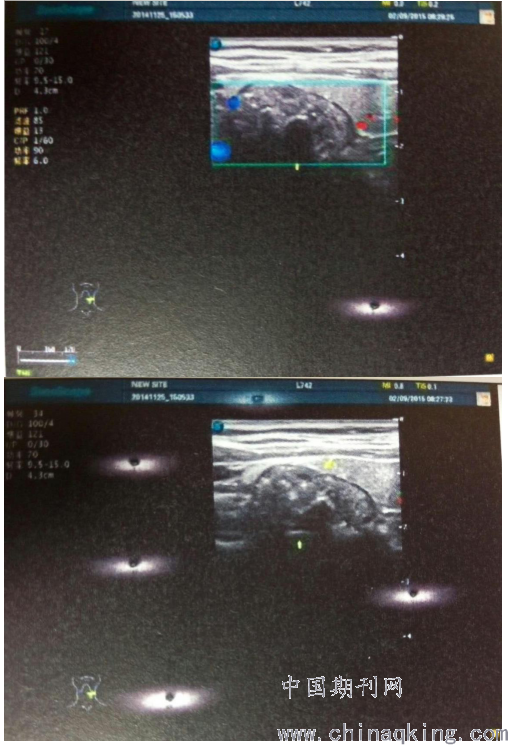

甲状腺超声提示:甲状腺大小形态结构正常,表面光滑,包膜完整,内部回声欠均匀,左侧叶可见一实性结节,大小约27mm*13mm,边界尚清,其内可见多个强回声光斑;右侧叶未见明显异常团块回声;双侧颈动脉旁未见明显异常肿大淋巴结回声。甲状腺超声诊断意见:甲状腺左侧叶实性结节(伴钙化灶)。

本例误诊原因分析:(1)本病较少见,临床上多数患者无明显症状,临床医师认识不足,缺乏经验;(2)甲状腺与颈段食管在解剖上紧密相连,咽食管憩室质地柔软,与甲状腺粘连,触诊不清晰;(3)无症状患者一般是在常规体检时发现包块,超声医师重视度不够,且超声诊断有自身局限性,容易出现多种假象,尤其是伴有甲状腺病变、憩室炎症或憩室内存在内容物时,超声影像难以明确肿物来源,可在超声中形成“甲状腺结节包膜”、“甲状腺肿块出血囊性变”或“甲状腺结节伴钙化”的假象[7]。